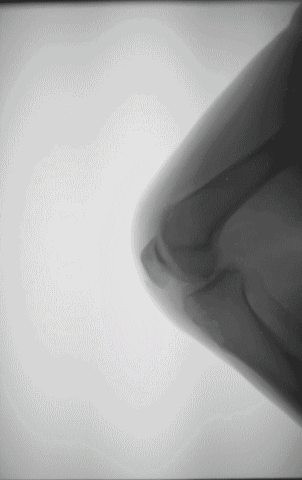

一、 跑步膝(髌骨疼痛综合症、髌骨软骨软化症),跑步膝的症状有:膝盖或膝盖下疼痛,在久坐后站起或上下台阶时疼痛加剧,屈膝时感到摩擦或有弹响声,严重时膝盖触痛,伸展时也痛。(注意,如果只有弹响,而膝关节活动时不疼痛,活动范围也无受限,则不用太担心)

疼痛位置:以膝盖骨为中心,基本就是膝盖中心及其周围。如图红圈位置: